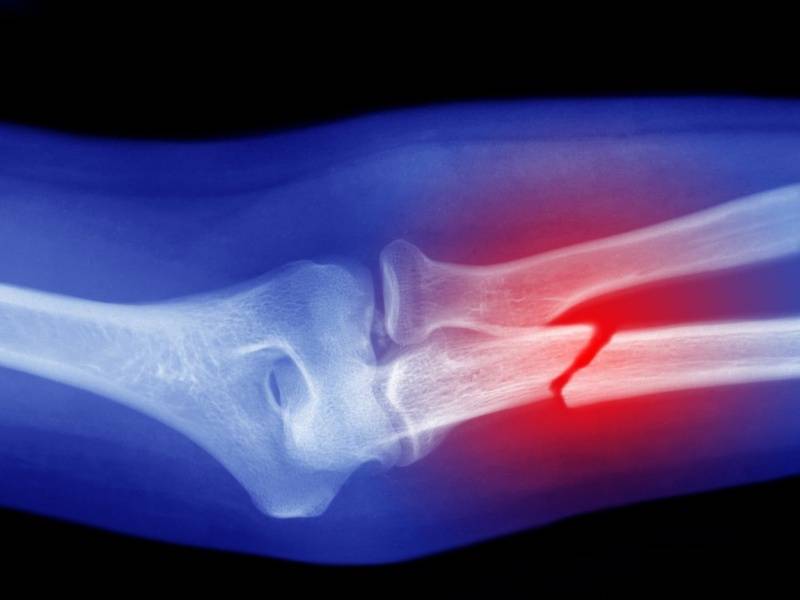

به گزارش سیناپرس، دانشگاه کینگز کالج لندن در پژوهش جدیدی نشان داده است پشم میتواند جایگزین مؤثر و پایداری برای موادی باشد که در حال حاضر برای ترمیم استخوانهای آسیبدیده استفاده میشوند.

پژوهش جدید دانشمندان «کینگز کالج لندن»(King’s College London) نشان میدهد کراتین که یک پروتئین طبیعی بهدستآمده از پشم است، از بازسازی استخوان حیوان زنده پشتیبانی میکند و به تولید بافت استخوانی میپردازد که نسبت به استاندارد طلایی کنونی، شباهت بیشتری به استخوان طبیعی و سالم دارد.

گروه پژوهشی کینگز کالج لندن، کراتین بهدستآمده از پشم را در مدلهای حیوانی آزمایش کردند و دریافتند که این ماده قادر به هدایت رشد استخوان جدید در نواحی آسیبدیده است. دکتر «شریف الشرکاوی»(Sherif Elsharkawy) از پژوهشگران این پروژه گفت: ما واقعاً هیجانزدهایم که برای اولین بار نشان میدهیم چگونه یک ماده مبتنی بر پشم با موفقیت برای ترمیم استخوانهای یک حیوان زنده آزمایش شده است.